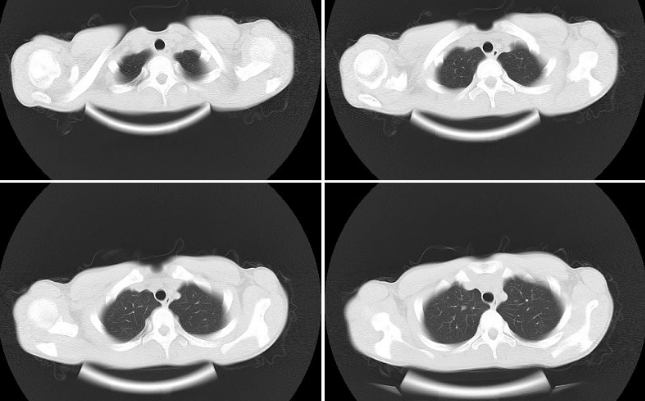

X線檢查、胸部MRI

漏斗胸圖片

Q:先天性漏斗胸診斷依據

A:先天性漏斗胸診斷依據一般可以根據胸廓的視診、胸部CT、心電圖等方面的檢查來確認,具體可以到當地的醫院做了解。先天性漏斗胸的形成可能是與遺傳、或者是伴隨有某種先天疾病導致的。患者通常表現為前胸凹陷,肩膀前伸,略帶駝背等症狀。輕微的畸形可以暫時……